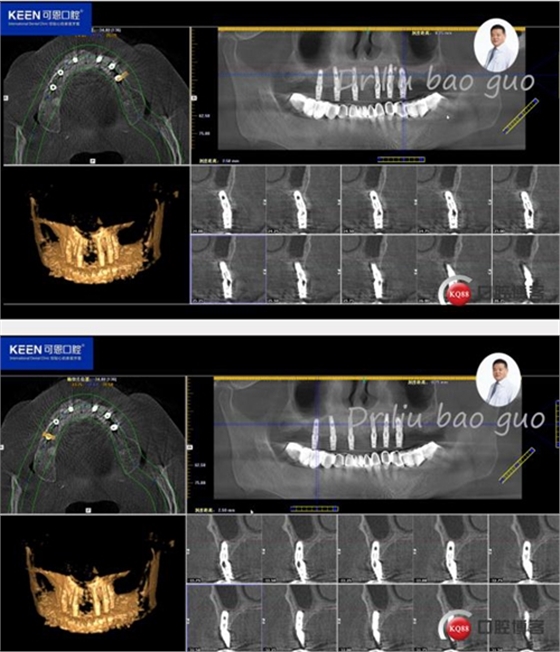

術(shù)后照片